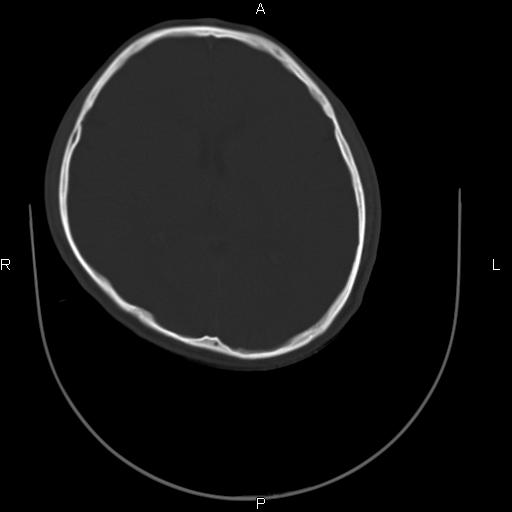

标题: CT27115:大家看一看,这孩子的颅骨表现?

两名中学生打架,脑质内未见异常,未上传。

感觉第2个颅缝密度高,额顶部板障有点厚,正常变异?地中海贫血?